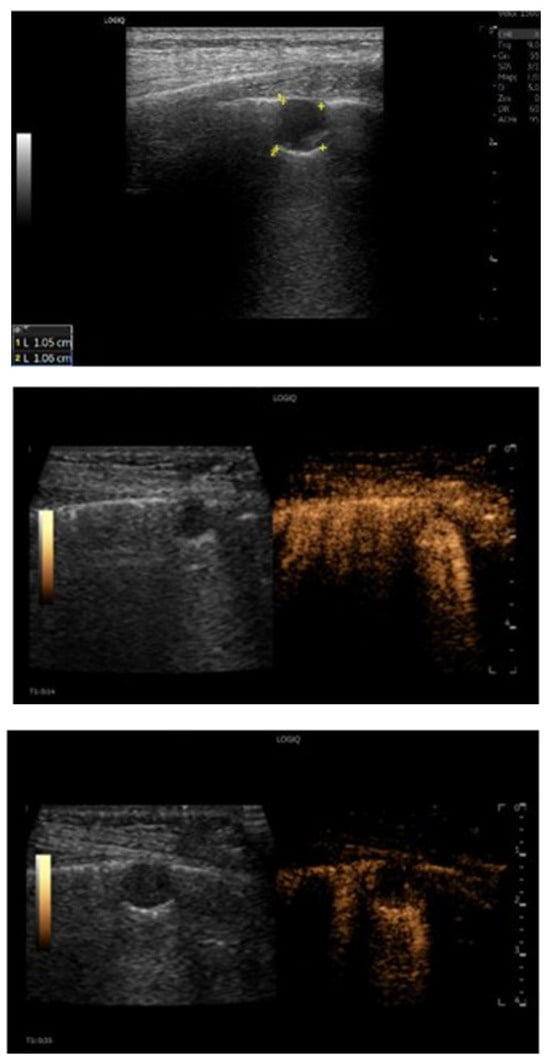

Application value of gastric contrast ultrasonography in gastric tumors